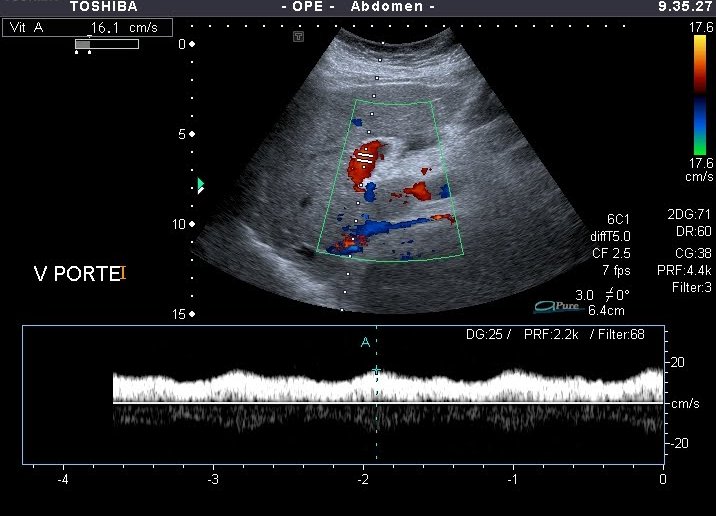

A v. portae bal oldali fotorzseben es a distalisabb agaiban jo aramlas (12 cm/s felett az atlagos sebesseg, 15cm/s felett a maximalis sebesseg)

A v. portae jobb oldali agaban a magas ellenallasnak megfelelo lassult aramlas (12 cm/s alatti ertek)

A v. portae aramlasa 15 cm/s maximalis es 12 cm/s atlagos sebesseg alatt szamit lassultnak.